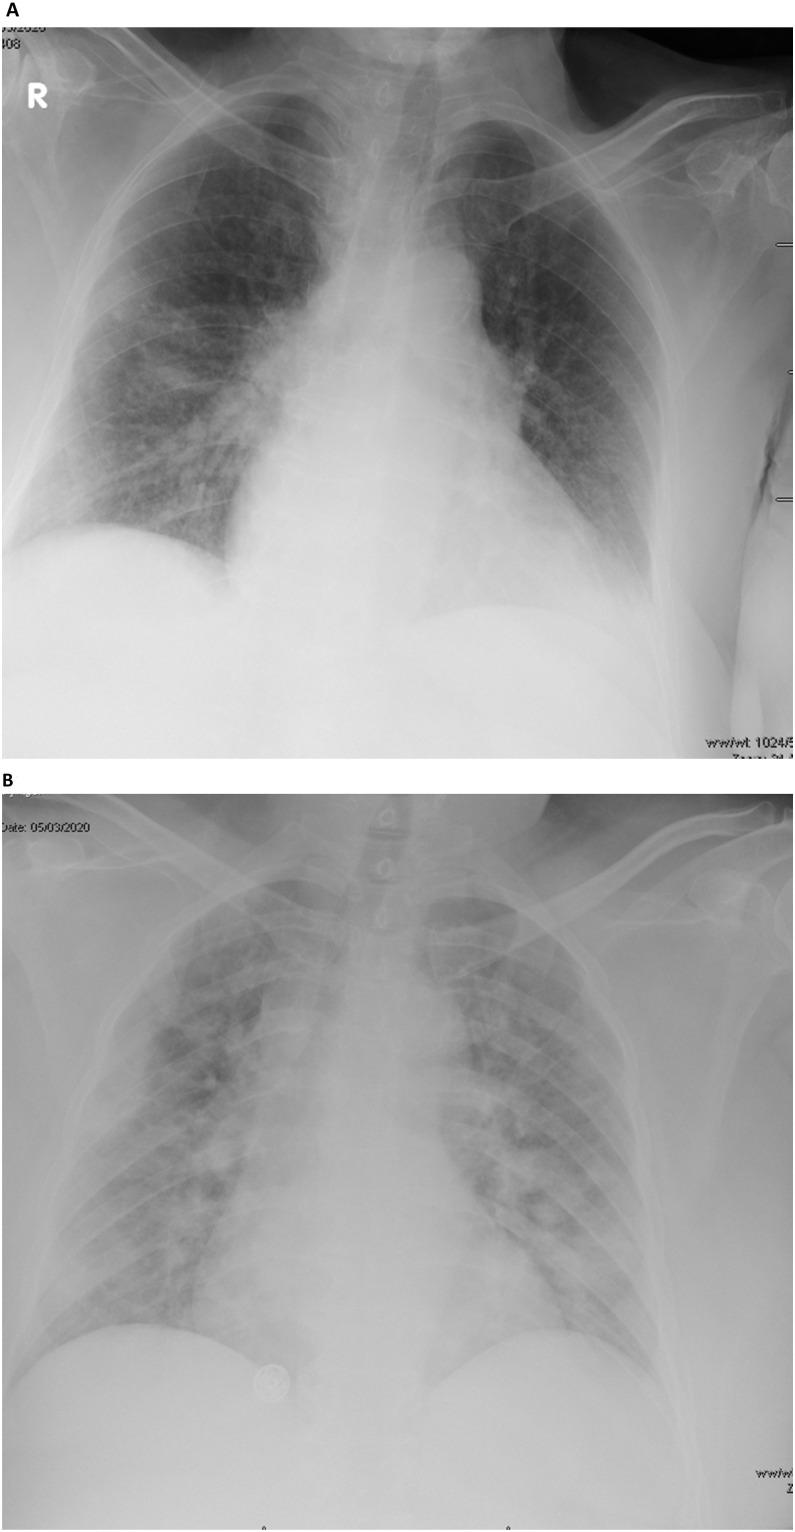

From March 1st, 2020 to April 5th, 2020 we identified a total of 82 adult COVID-19 patients. The median age of the patients was 50 years, with a range of 30 to 60 years and most of patients were female 54 (65.9%). Of all the patients, 29 (35.4%) were contacts and 43 (52.4%) were returning travelers, mainly from Iraq (65% of the total returning travelers). Comorbidities were present in 50% of patients, G6PD deficiency in 33%, hypertension in 27%, and diabetes mellitus in 26%. Chest radiographs were abnormal in 46% of symptomatic and 15.5% of asymptomatic patients (P value = 0.0035). Of all patients, 4 (4.87%) required intensive care admission. There was no significant difference in time to negative RT-PCR with mean days to negativity of 13.6 and 16.9 for asymptomatic and symptomatic group, respectively (P value = 0.42).

从 2020 年 3 月 1 日至 2020 年 4 月 5 日,我们共发现 82 例成年 COVID-19 患者。患者的中位年龄为 50 岁,范围为 30 至 60 岁,大多数为女性(54 例,占 65.9%)。所有患者中,29 例(35.4%)为接触者,43 例(52.4%)为归国旅行者,主要来自伊拉克(归国旅行者总数的 65%)。50%的患者存在合并症,33%存在 G6PD 缺乏症,27%存在高血压,26%存在糖尿病。46%的有症状患者和 15.5%的无症状患者的胸部 X 线异常(P 值=0.0035)。所有患者中,有 4 例(4.87%)需要重症监护病房收治。无症状组和有症状组的 RT-PCR 转阴平均时间分别为 13.6 天和 16.9 天,差异无统计学意义(P 值=0.42)。